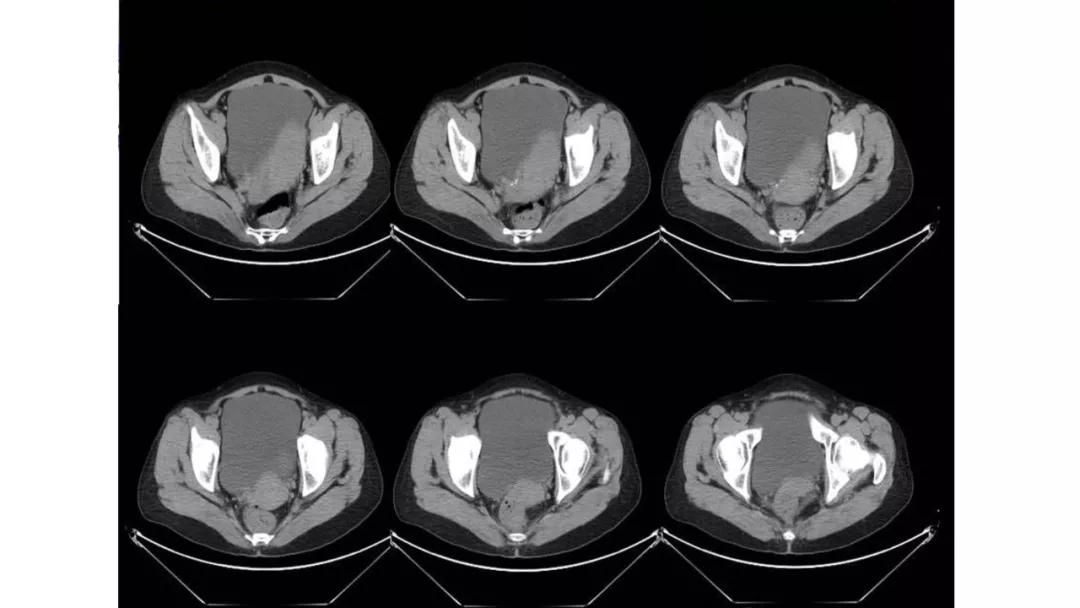

上皮性肿瘤:最常见,恶性多(卵巢癌),良性少。好发于50Y以上,发现时多为中晚期。多呈囊性或以囊性为主的囊实性肿块,完全实性者少见。形态多数不规则,边界模糊,囊壁及房间隔常不规则增厚,菜花样肿物或壁结节,囊实性区域分界不清,实性肿瘤常有不规则低密度或坏死区,可有边界模糊沙粒状或块状钙化,中-高度强化。良性者边界清晰,囊壁薄光整,无壁结节,实性部分呈无或轻度强化。